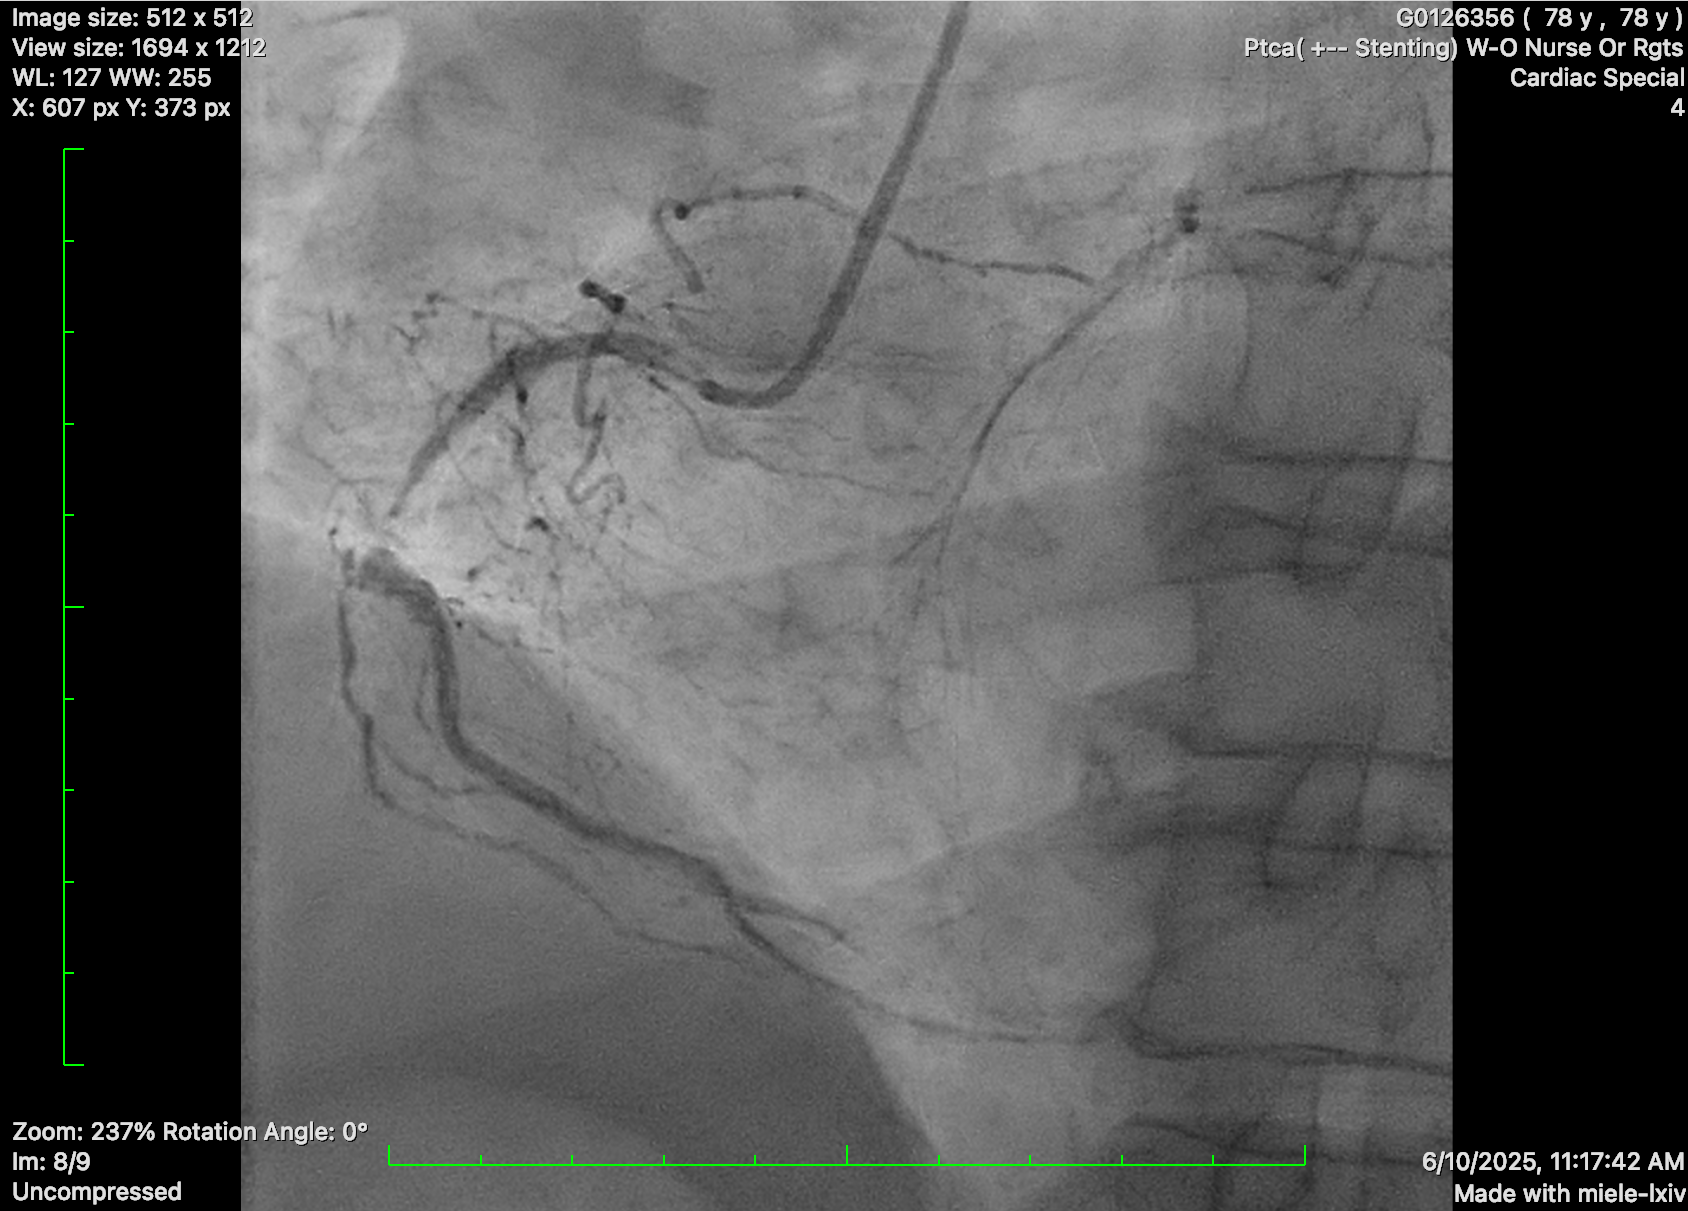

Impella CP inserted due to underlying poor LVEF and intention for rotational atherectomy in the left main.

PCI to RCA: JR 4.0 guide catheter. Critical RCA lesion crossed with Fielder XT-R supported by microcatheter. Predilated with semi-compliant balloon and 3.0/40, 3.5/22 and 3.5/9 stents deployed. Post dilated with NC 3.25 balloons.

PCI to LCA: EBU 3.0 7 Fr guide catheter. Successful wiring to distal LAD with workhorse wire. Unable to cross SC 1.0 balloon. Exchanged for Rotawire Extra Floppy. 1.25mm burr for rotational atherectomy with significant decelerations. Still failed to deliver SC 1.0 and 1.5 balloon. Upsized to 1.5mm Rotaburr. Further dilated with SC 1.5 and 2.0 balloon, then shockwave with 2.5 balloon and further predilatation with NC balloon. DES 2.25/30, 3.0/18 and 3.5/24 deployed. Post dilatation with NC 4.0 and 3.5 balloon.